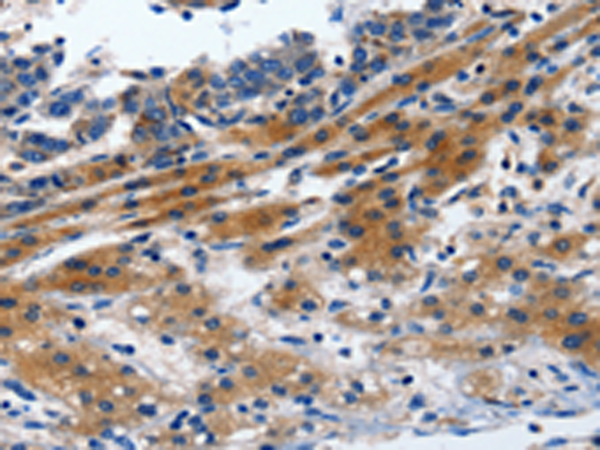

分类: 科研抗体货号: P04084别名: CD11A, LFA-1, LFA1A应用: IHC反应种属: Human